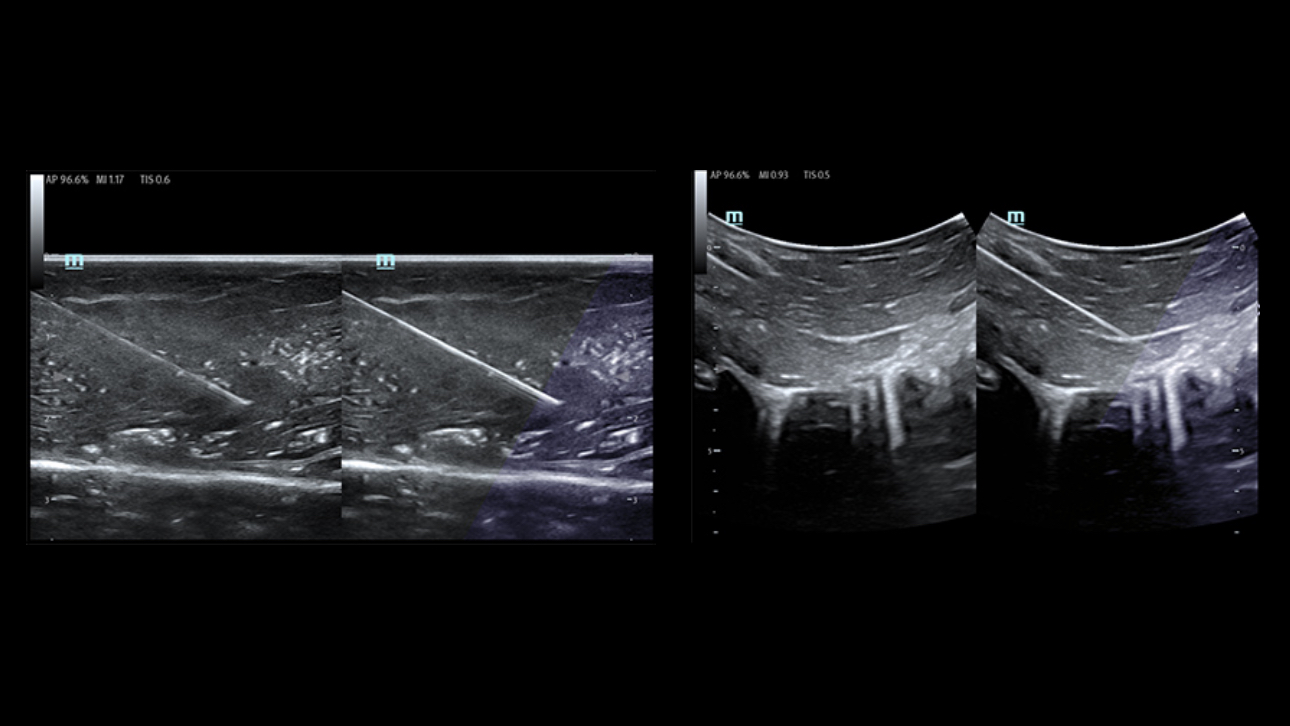

Funkcje wspomagaj?ce operatora podczas wk?u?

Obrazy kliniczne